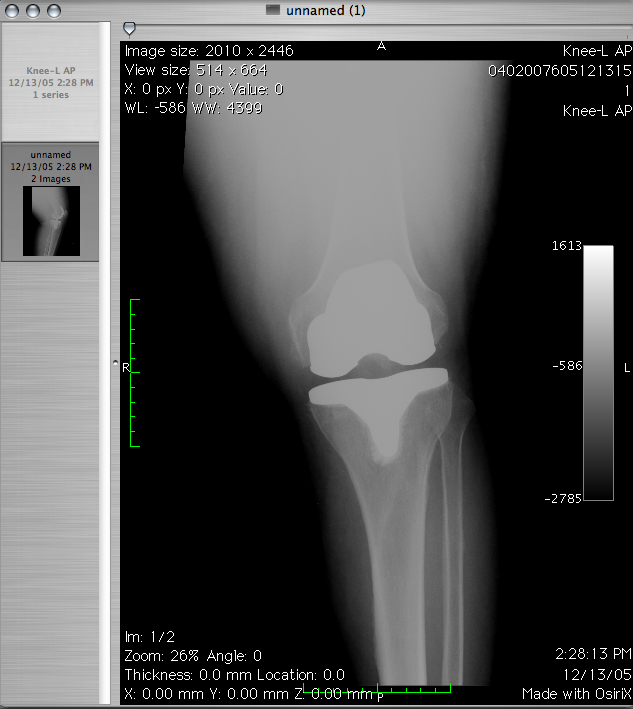

Obecnie medycyna bardzo szybko się rozwija. Możemy leczyć bardzo wiele chorób. Tworzy się sporo miejsc, …

Jedną z szybciej rozwijających się dziedzin jest rehabilitacja. Nie wiedzieliśmy kiedyś jak wielki potencjał w …